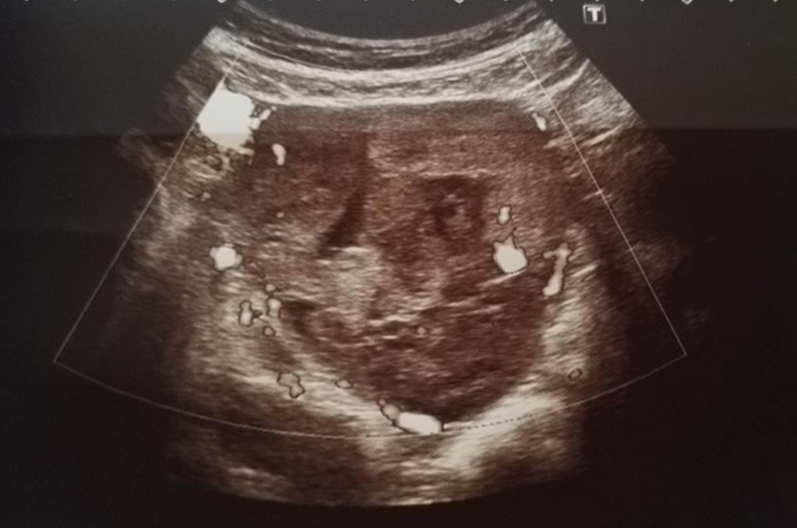

A 52-year-old menopausal woman who was referred for a palpable right adnexal mass detected on routine vaginal examination. A transvaginal scan revealed a right adnexal complex mass of mixed echogenicity measuring 6.6×5.7×8 cm (Figure 1), (Figure 2) with increased vascularity on colour doppler (Figure 3). The patient had no medical or surgical history of note.

Figure 3: The lesion with increased vascularity on ultrasound scan.